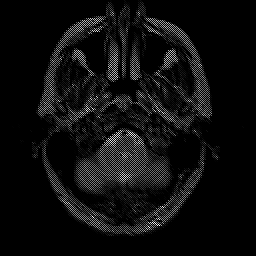

glioma overlay -- Slice #3

[Home][Help][Clinical] Slice 3